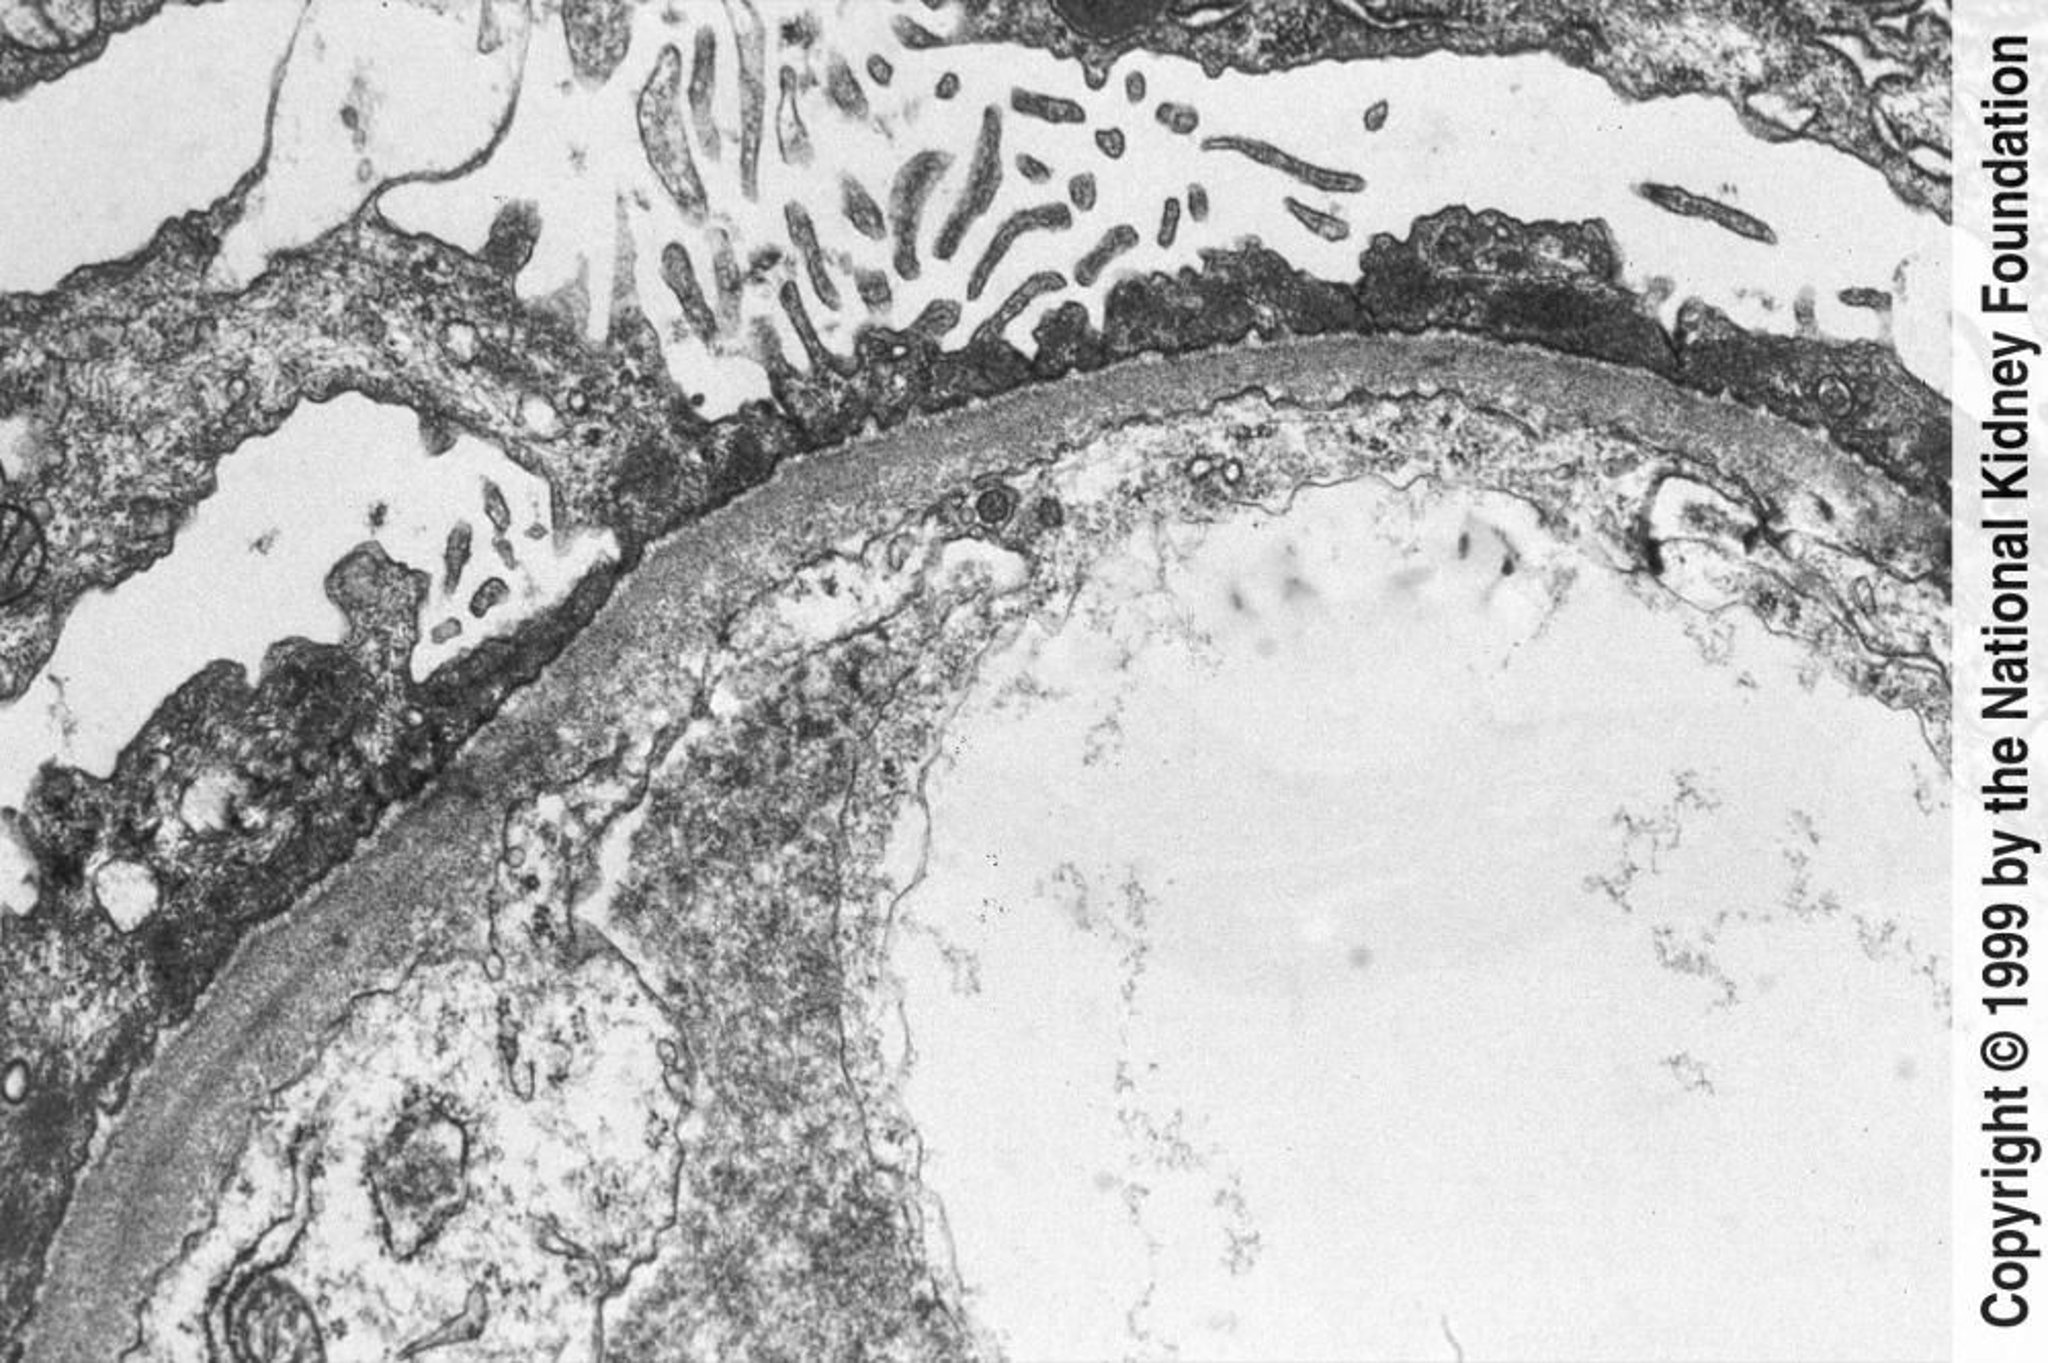

In der Transmissionselektronenmikroskopie ist eine diffuse Auslöschung der Podozyten zu erkennen (×800).

Image provided by Agnes Fogo, MD, and the American Journal of Kidney Diseases' Atlas of Renal Pathology (see www.ajkd.org).